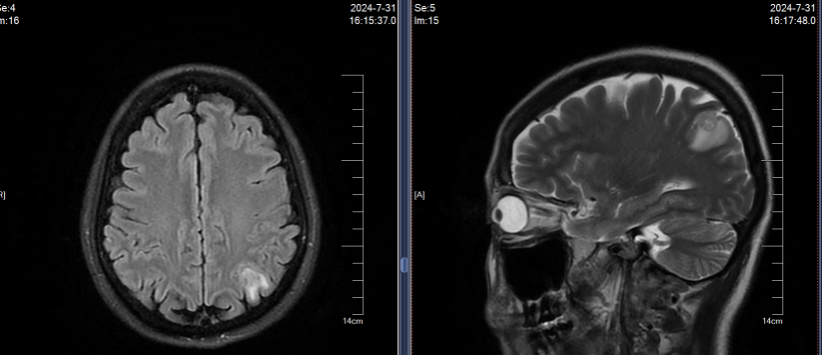

2024年7月30日胸部CT示:左上肺术区新增结节,两肺多发实性结节较前增多,肝S7新增结节;7月31日头颅MRI示左侧顶叶、小脑半球新增转移灶。结合影像及病史,确诊为ALK阳性晚期NSCLC复发伴多发转移(图1)。